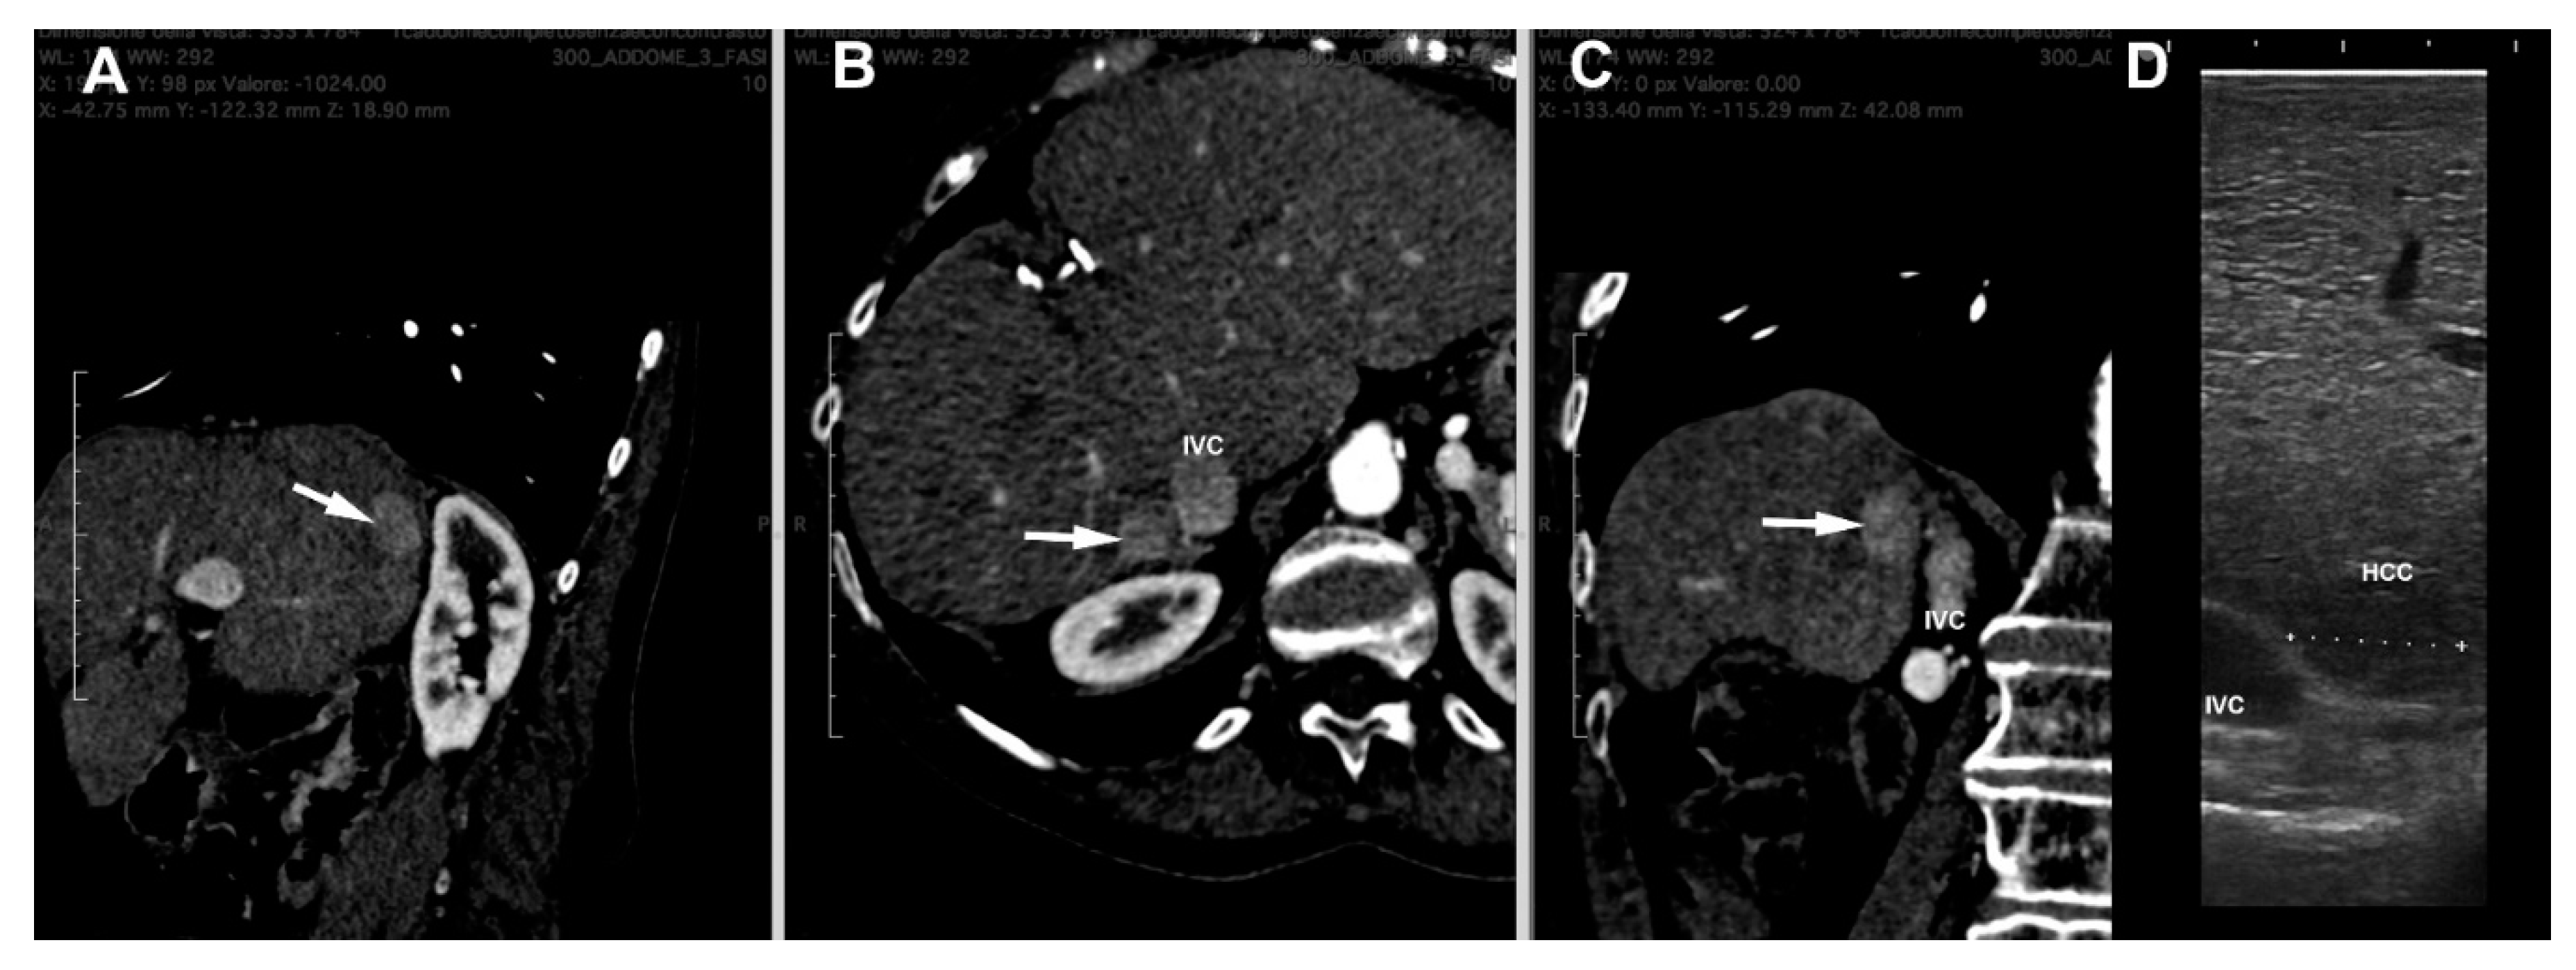

4. LUS Evaluation